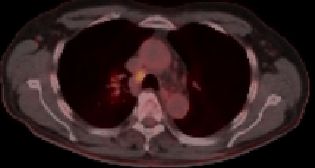

| PET-CT | Paratracheale Lymphknotenmetastase eines Adenokarzinoms des rechten Lungenoberlappens mit Infiltration der dorsalen Brustwand. |